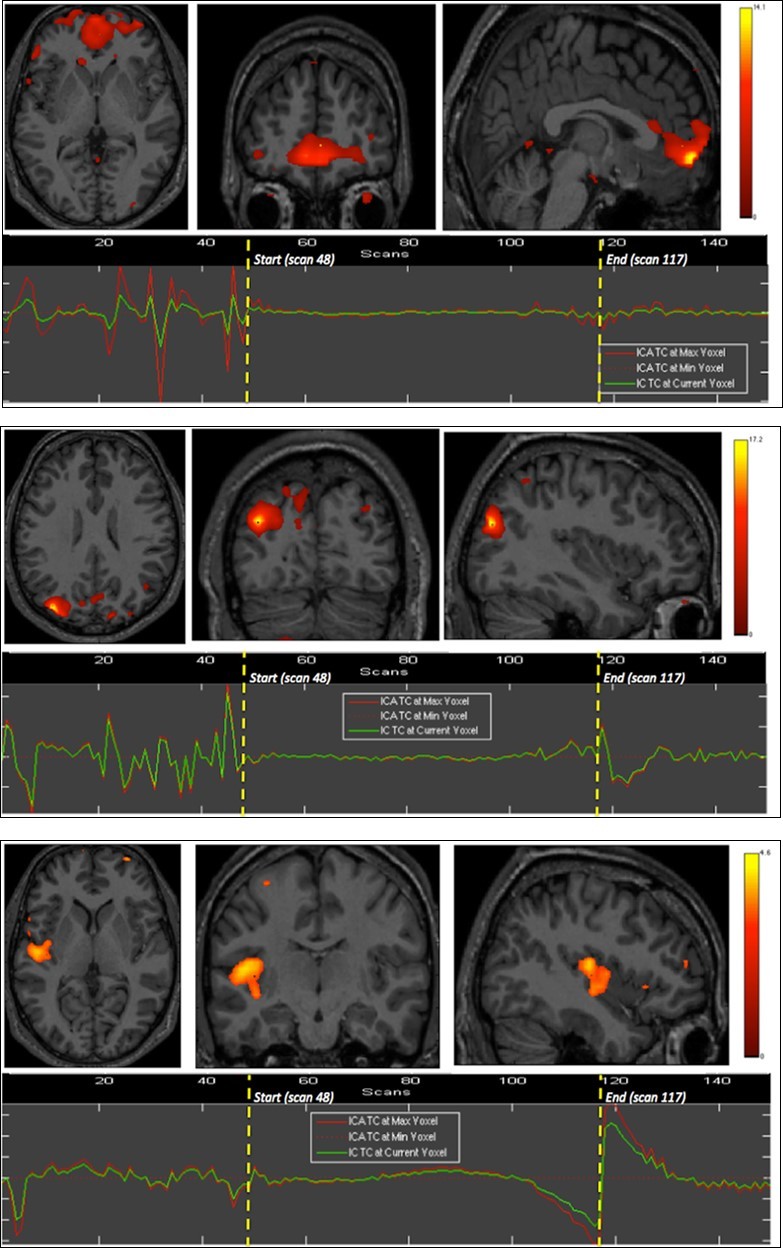

Right insula, bilateral orbitofrontal and right inferior parietal cortices were eloquent during the second breath holding (Figure 2).

Figure 2.Second experiment showing BOLD time courses and activation of ventromedial prefrontal cortex (upper row) and inferior parietal cortex including the angular gyrus (middle row) and the supramarginal gyrus (lower row).

The apnea period was obviously recognizable on the time course of the BOLD signals graphs because of the striking change of the curves from breathing to apnea and after apnea, with very low fluctuations during apnea. Within eloquent brain areas TC curves showed various patterns: (i) high fluctuations mainly in the second half of apnea in the dorsal pons only (Figure 1-1st row), (ii) very low fluctuations with deep depression at the end of apnea in the cerebellum (Figure 1-2nd row) as well as in the supramarginal gyrus (Figure 2, lower row), less marked in occipital areas (figure 1-4th row), and (iii) flat curve in dorsomedial prefrontal (Figure 1-3), ventromedial prefrontal (Figure 2-upper row) and inferior parietal areas (Figure 2-middle row). The eloquent areas disclosed during both experiments are mapped on a brain mesh as nodes of both networks (Figure 3).